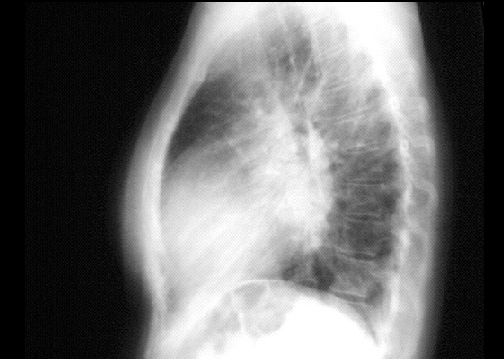

PA view

The PA view demonstrates left atrial enlargement, reflected by the double contour within the heart border, an elevated left mainstem bronchus and an enlarged left atrial appendage, causing straightening of the left heart border. Note also that the cardiothoracic ratio is greater than 50%, reflecting cardiomegaly.